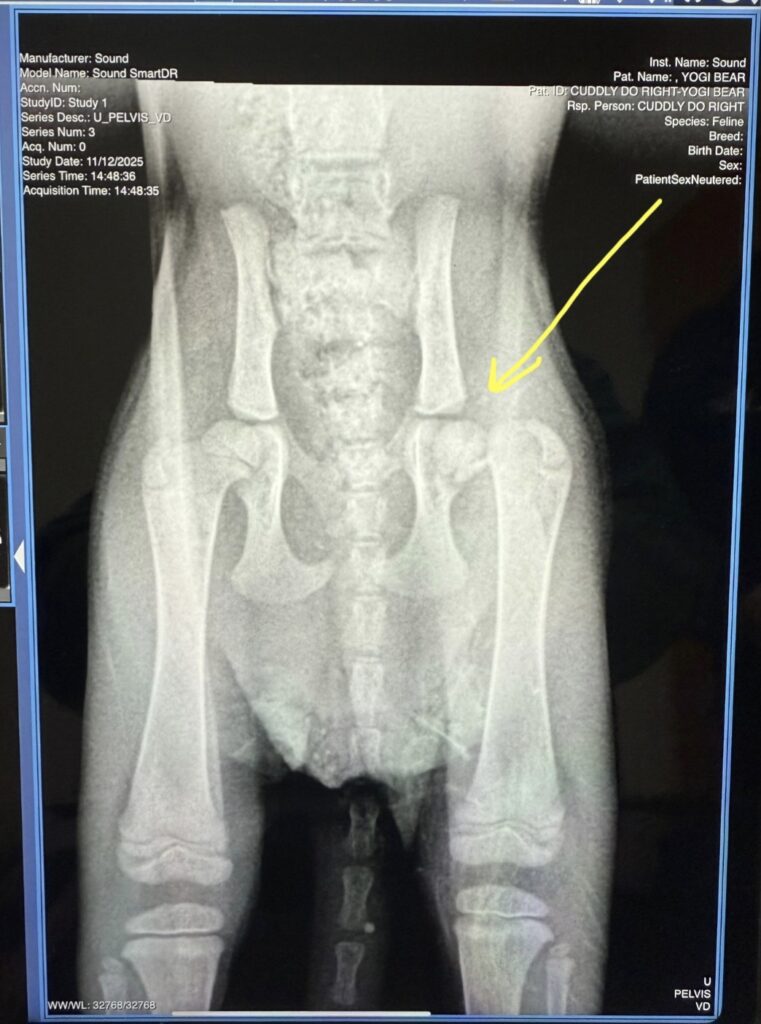

The question of what’s causing her to react in pain to having her left foot/leg touched and why she needs human assistance to support her tail end when she potties was answered, too. For the grand sum of $385, Yogi got her first poke and prod, a vaccination, some pyrantel… and a couple xrays. She has a fractured and dislocated femur. 😱

Yogi will need surgery to resolve this. The first estimate we’ve received is $1500-1800. We are seeking a second estimate and will update you about that and everything else related to Yogi Bear!